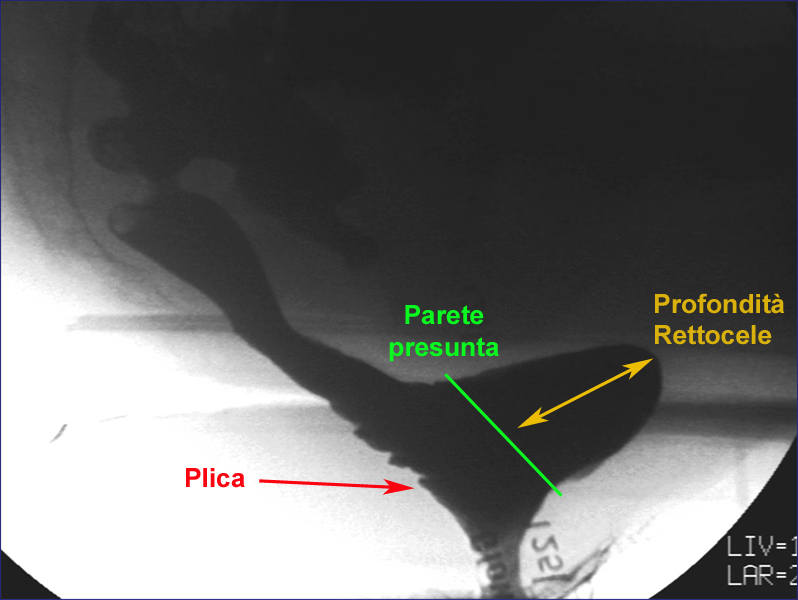

La profondità di un rettocele tipicamente si quantifica nella

fase di massima “straining”

calcolando la protrusione della parete

rispetto all’asse del canale anale; in

realtà ci sembra più corretto calcolarla

nella fase espulsiva terminale in quanto la

sintomatologia del rettocele si verifica

tardivamente essendo direttamente

proporzionale al residuo indovato. Inoltre

l’aumento di pressione nella ampolla nella

fase iniziale della defecazione è tale da

far assumere un aspetto “bombato” al

serbatoio stesso.

Fig. 5 - fase

espulsiva avanzata |

espulsiva finale |

|

La parete anteriore dell’ampolla rettale si

estroflette a formare una sacca di

dimensioni progressivamente maggiori. |

Nel retto residua abbondante quantità di materiale.